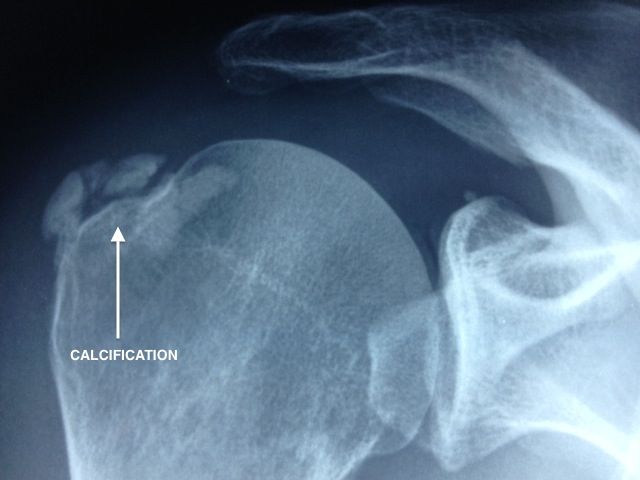

Dans un premier temps, il est indiqué de réaliser des clichés radiographiques, associés à une échographie.

Puis, il pourra être utile de faire une IRM ou un arthroscanner, pour localiser la calcification et évaluer sa taille par rapport à l’épaisseur du tendon.

Les calcifications sont situées dans le tendon du sus-épineux dans 80 % des cas. Dans 15 % des cas, elles se situent au niveau du tendon infra-épineux et dans 5 % des cas, au niveau du tendon sous-scapulaire.

On définit 3 types de calcifications :

• Calcifications type A : denses, homogènes, à contours nets.

• Calcifications type B : denses, homogènes, multilobées à contours nets.

• Calcifications type C : inhomogènes, à contours flous disséminée dans le tendon.